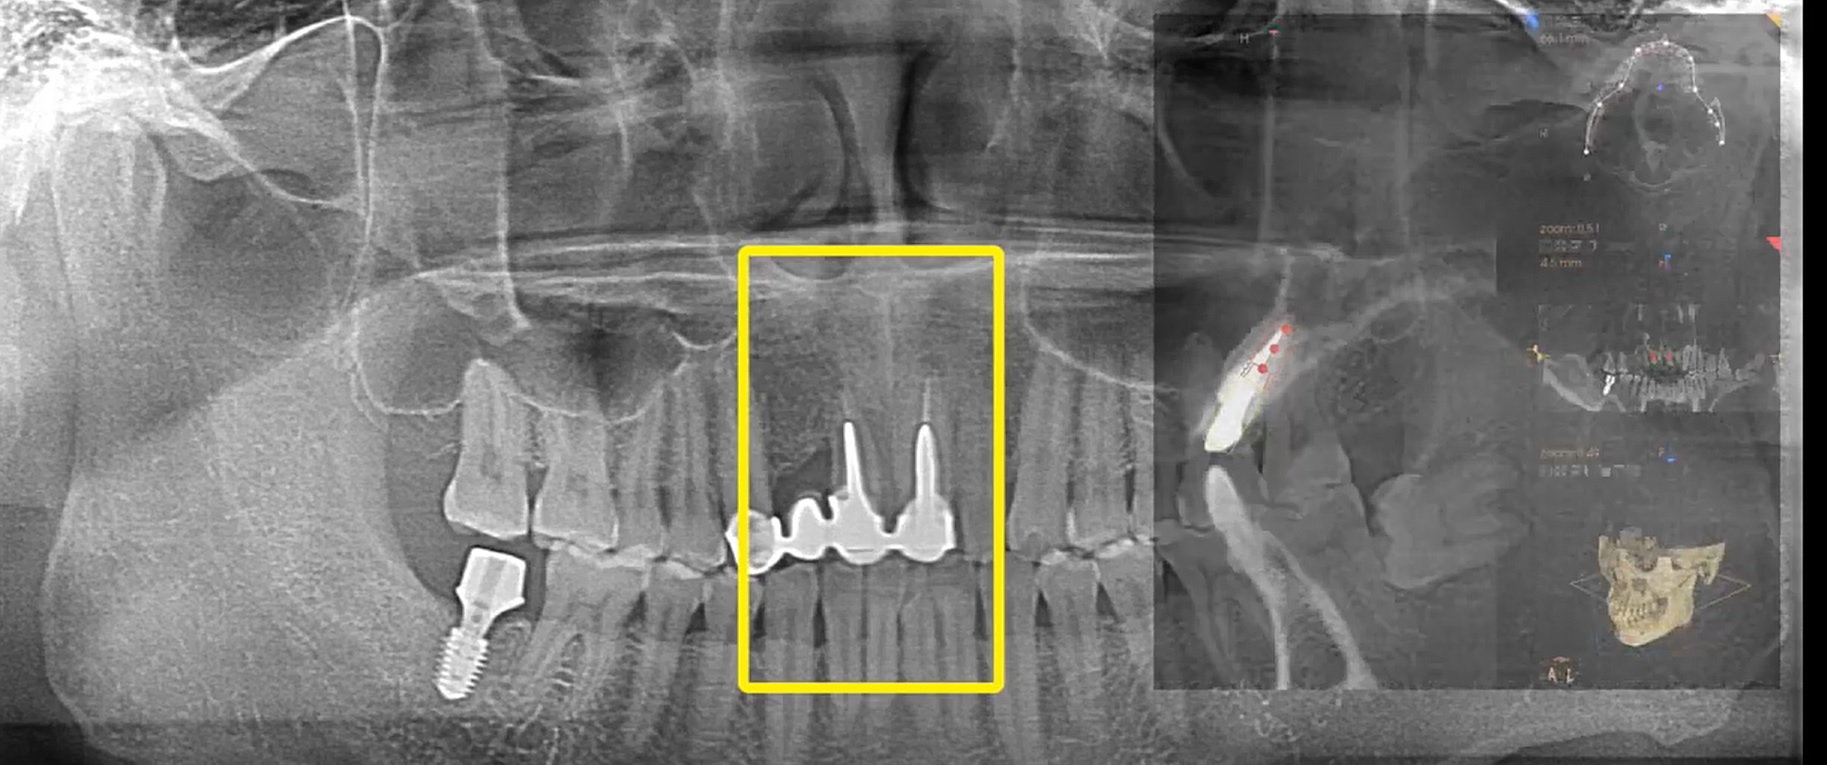

Bone filling into the bottom of deepest thread at 8.0mm AnyRidge fixture

Dr. Kwang Bum Park,Single replacement,Bone regeneration,Mandibular Posterior,#36,Immediate Placement,GBR,AnyRidge,Mega-Oss,Bone Plus, KnifeThread,Extraction socket,Initial stability,Allograft,Osseointegration,Clinical Case